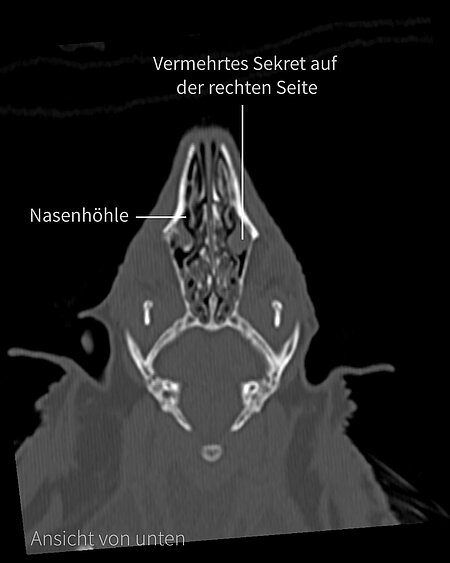

Um die Ursache für das Augenproblem herauszufinden, war sie in der Tierärztlichen Hochschule Hannover im CT. Auf den Bildern sind einzelne Aufnahmen aus der Computertomographie vom Kopf des Igels zu sehen. Man sieht keine Fraktur der Schädelknochen, die hätten ursächlich sein können, aber etwas vermehrt Sekret in der rechten Nasenhöhle.

Inzwischen verheilt das Auge gut. Zudem haben wir im CT gesehen, dass sie lockere Zähne hat. Deshalb wurden ihr während einer Zahnsanierung zwei lockere Backenzähne entfernt. Abgesehen davon sind die Zähne in gutem Zustand und werden ihr weiterhin gute Dienste leisten.